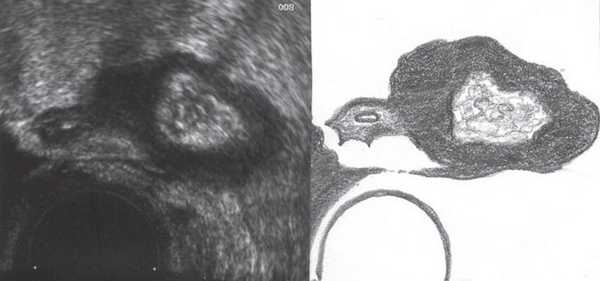

Рис. 3. Эхографическая картина дивертикулита. Трансабдоминальное исследование конвексным датчиком 3,5 МГц.

При трансвагинальном УЗИ (рис. 4) также визуализировался фрагмент толстой кишки с утолщенными гипоэхогенными стенками и несколькими округлыми дивертикулами до 1 см в диаметре. Контуры одного из дивертикулов были неровными, он имел звездчатую форму. Отмечались утолщение и повышение эхогенности околокишечной жировой клетчатки по сравнению с контралатеральной стороной. При осмотре в режиме УЗ ангиографии утолщенная стенка кишки и дивертикулы были аваскулярными, окружающая клетчатка - гиперваскулярной.

Рис. 4. Эхографическая картина дивертикулита. Трансвагинальное исследование конвексным датчиком 7,5 МГц.